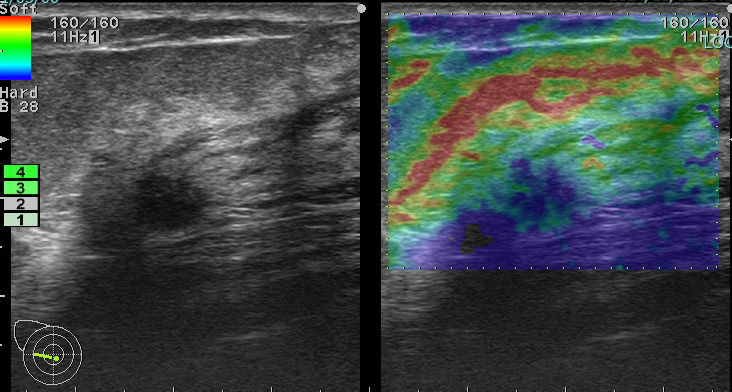

上に挙げた4つのエラストグラフィー

これが何を物語っているか?

エラストグラフィーは何か所見があった際に「これは怪しい!」と思わない限り追加で行わないものです。

これを実は4回も(昨年)行っていたのです。

つまり、(昨年も)その技師は「明らかに癌を疑っていた。」

この4枚のエラストグラフィーは技師の「これは怪しい所見です!是非要精査にしてください!」という心の叫びと言えるんだね!

まさに、その通り!

ただ、悲しいかな。技師さんのその「必死な思い」は、検診画像評価を行う医師には伝わらなかった。

結局、検診結果を出すのは(その画像を見て判断する)医師なのです!

正に診断の問題点1「画像評価」の過ちがここにありました。